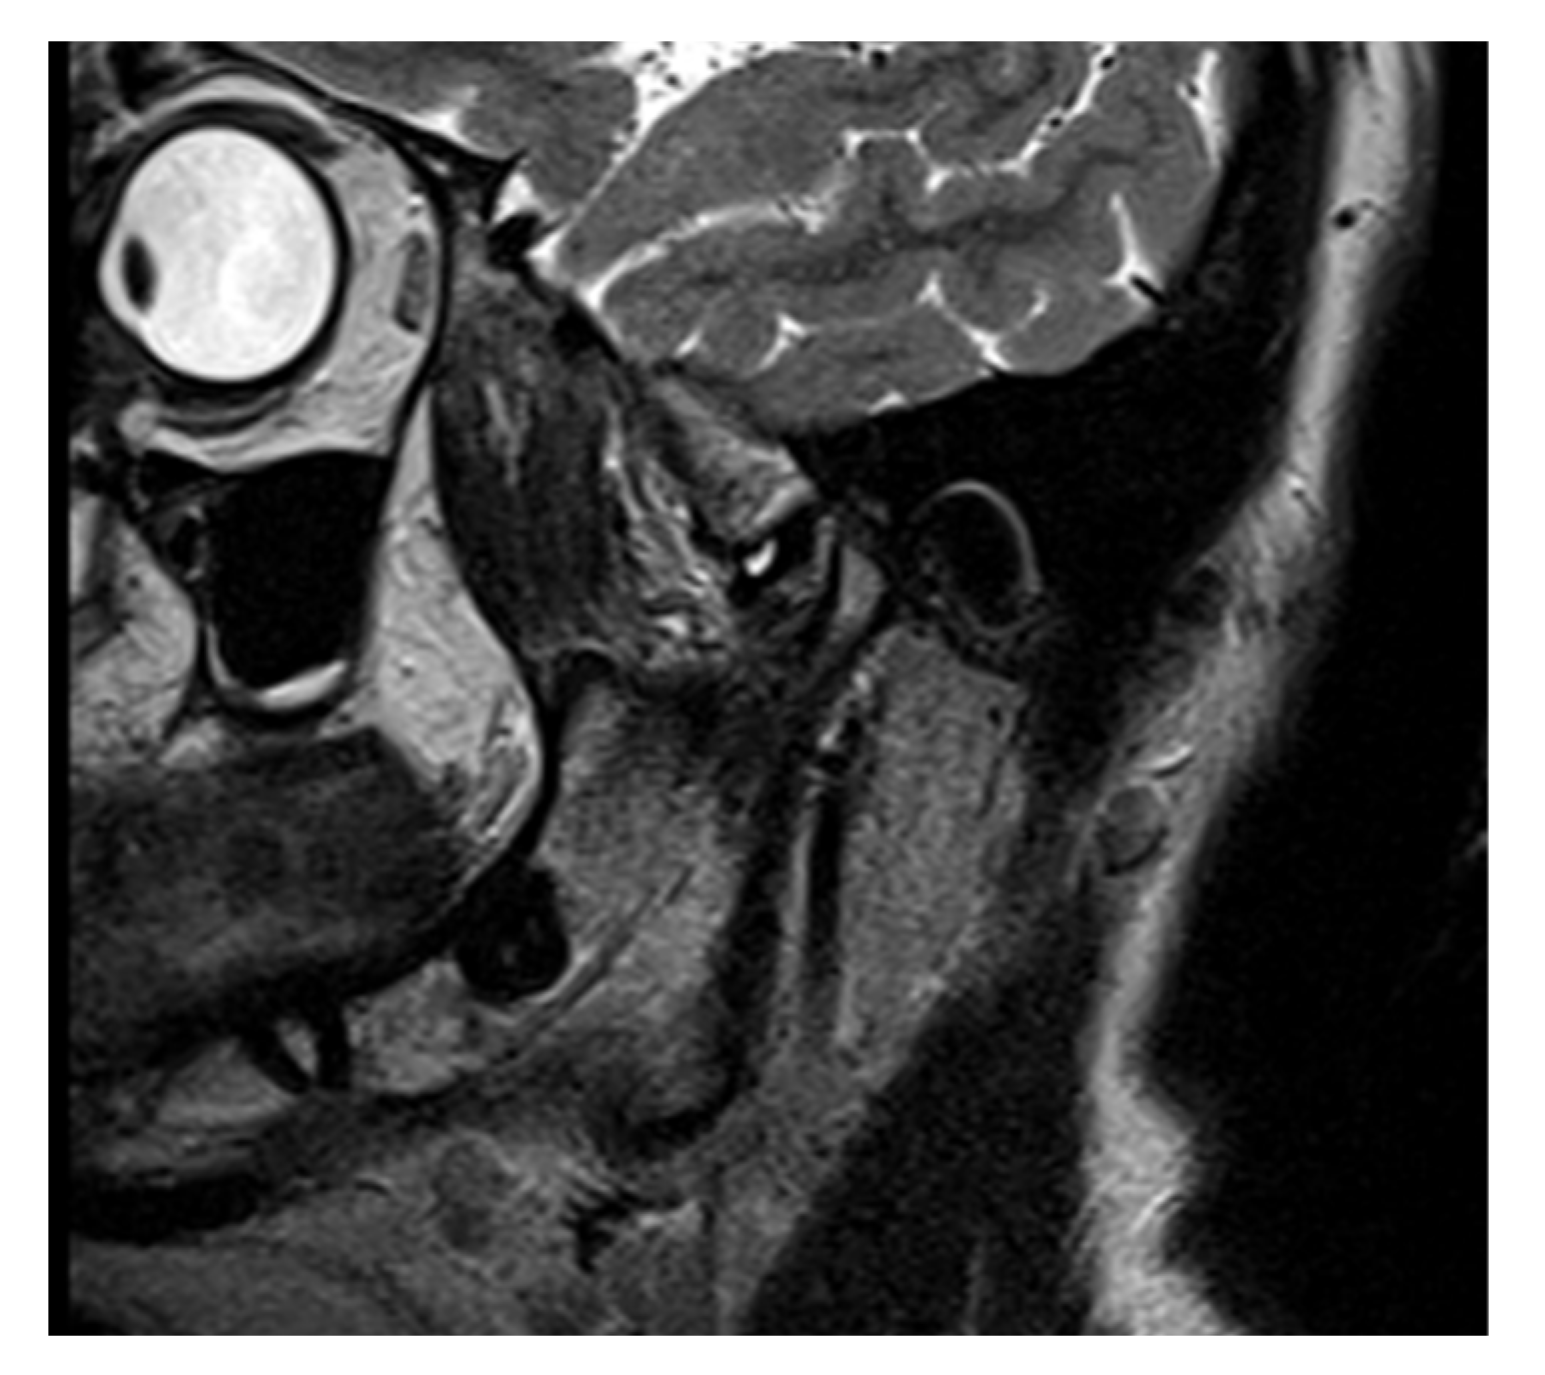

3.3. Case Report